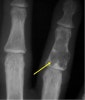

X-ray : 내연골종(Enchondroma)

신체의 다른 부위보다 수지골과 족지골에 호발하며, 골의 내부에서 연골을 형성하여 피지골을 밖으로 팽창시키며, 피질골을 뚫고 나오는 경우도 있습니다.

따라서 사소한 외력에 의한 병적 골절을 흔히 동반합니다.